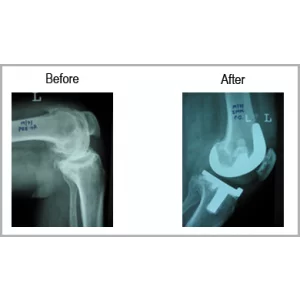

A male aged 71 years had severe both knee pain with great difficulty in walking. He had no medical illness but because of knee pain was socially disconnected. He had bow legs. After he had both knee replacement his legs became straight and able to walk long distance without any difficulty and support. He is able to drive two wheeler.